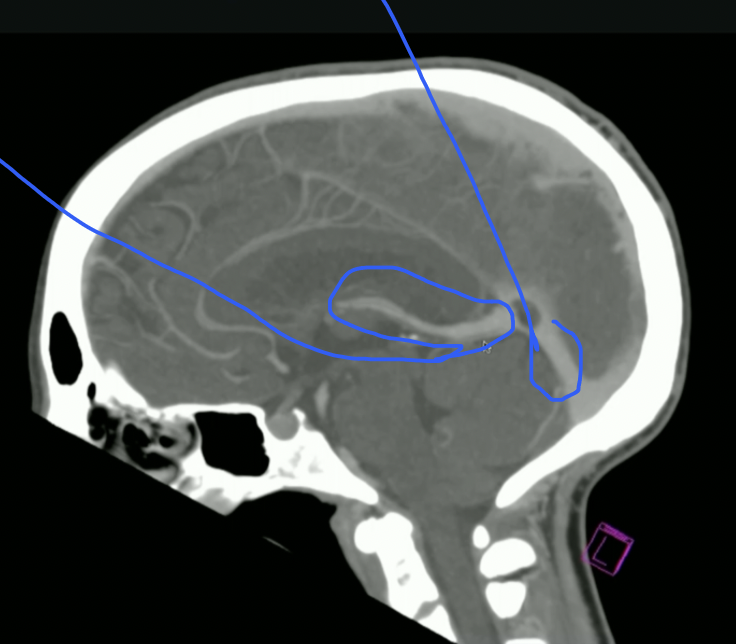

<p>What is this? + Function</p>

What is this? + Function

• Interventricular Foramen

• Communicates CSF from Lat Ventricles → 3rd Ventricle

<p>What is highlighted?</p>

What is highlighted?

• 3rd Ventricle

• CSF then goes to Cerebral Aqueduct

<p>What is Top + Bottom Circle + Arrow?</p>

What is Top + Bottom Circle + Arrow?

• Top: 3rd Ventricle

• Bottom: 4th Ventricle

• Arrow: Cerebral Aqueduct

<p>What Portion of the Corpus Callosum is this?</p>

What Portion of the Corpus Callosum is this?

• Genu